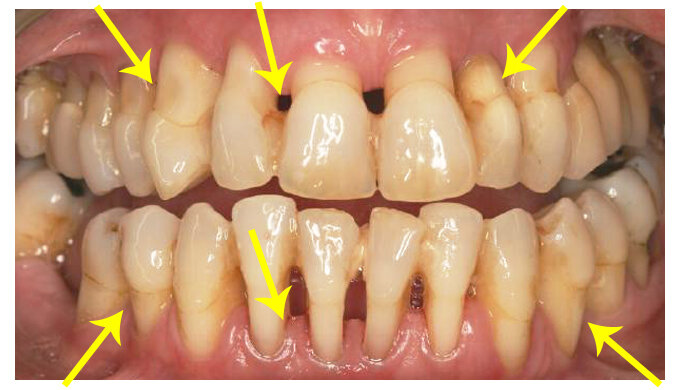

Клиническое проявление при пародонтозе. Жёлтыми указателями указана убыль костной ткани и бледная окраска десны, отсутствие видимых зубных отложений.

1. При лёгкой степени возникает зуд, жжение, «ломота» в разных участках челюсти. Также возможны чувства гипертензии и чувство подвижности зубов без видимой на то подвижности. Десна нормальной или бледной окраски, сглажены десневые сосочки. Зубы устойчивы и десна плотно прилегает к ним. Клинически проявляется генерализованная (распространённая) убыль десны до 3мм.

2. При средней степени пациенты отмечают, что их зубы стали больше по размеру, увеличиваются боковые межзубные расстояния, зубы начинают повышенно реагировать на температурные и химические раздражители. Десна может быть нормальной или бледной окраски. Также могут быть плотные наддесневые зубные отложения. Генерализованная убыль десны от 3х до 5ти миллиметров. На зубах в пришеечной части возникают клиновидные дефекты некариозного происхождения.

3. При тяжёлой степени возникает подвижность и перемещение зубов. Десна становится бледной и плотной, зубные отложения становятся пигментированными и плотными. Проявляется генерализованная убыль десны более 5мм. Может быть значительная подвижность и выпадение зубов.